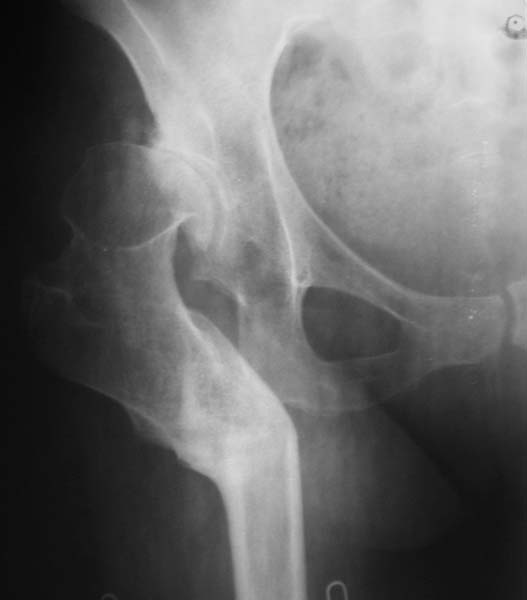

эндопротезирование после остеотомии по Шанцу

Уважаемые коллеги! Женщина, 35 лет В прошлом по поводу врожденного вывиха бедра перенесла операцию остеотомии по Шанцу

с удлинением правой ноги за счет бедра на уровне диафиза. В последнее время прогрессируют боли в правом тазобедренном суставе, порочное положение правой ноги, затруднена ходьба. Вопросы: 1) Целесообразно ли эндопротезирование правого тазобедренного сустава? 2) Целесообразный ли следующие действия: канал бедренной кости предполагаем вскрыть для введения ножки протеза на высоте угловой деформации, предполагаем низведение большого вертела с мышцами; протез будет подобран индивидуально, предполагается умеренная версия? В приложении рентгенограммы и трехмерная КТ. В цветном и более качественном варианте КТ размещена здесь